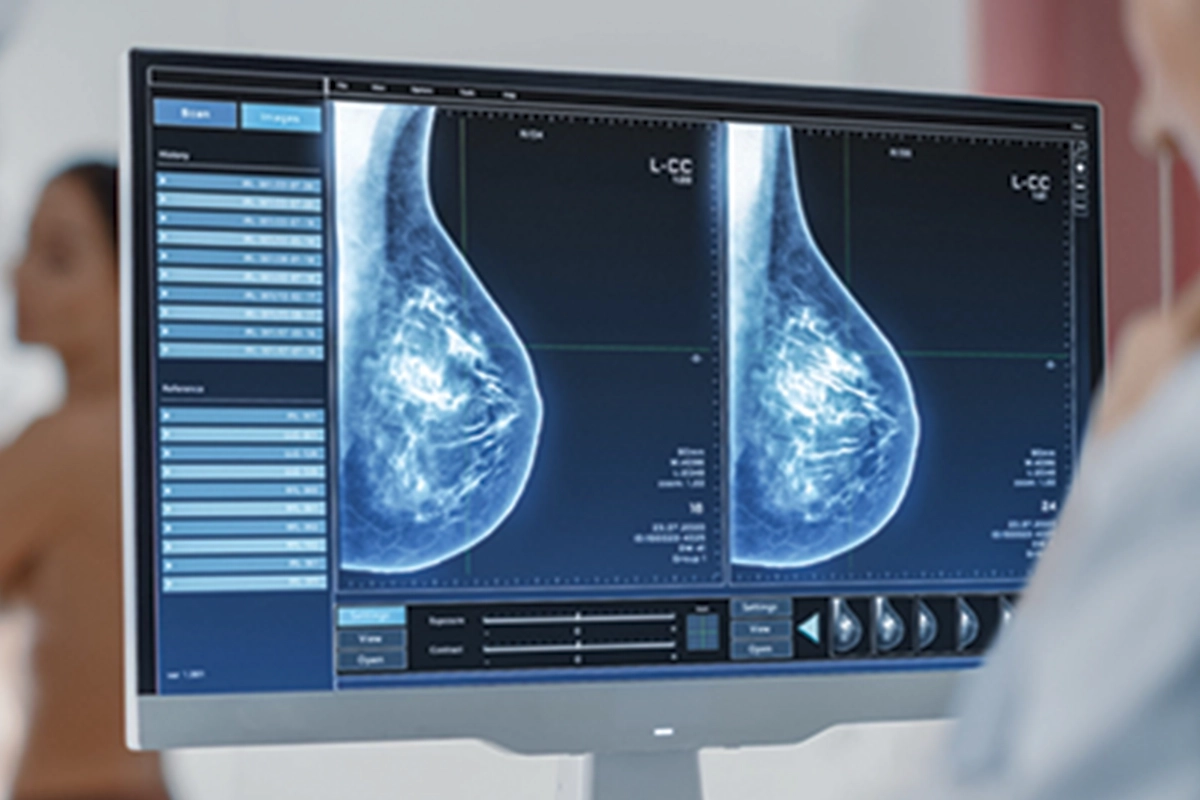

“40 YAŞINDAN İTİBAREN YILDA BİR KEZ MAMOGRAFİ ÇEKTİRİLMESİ GEREKMEKTEDİR “

Meme kontrolünün nasıl olması gerektiğini anlatan Poçan, “Memedeki problemleri tespit etmek için yaş fark etmeksizin, kendi kontrollerimizi aksatmamalıyız. Kontrollerde bir problem tespit ettiğimizde ya da kırk yaş üstünde ise bir hekim tarafınca kontrol, meme ultrasonu, gereklilik halinde mamografi veya meme MRG ile tetkikleri gerekmektedir. Ülkemiz sağlık politikalarınca mamografi ön planda tutulsa da teknolojik gelişmelerin ultrason cihazlarında yapmış olduğu belirgin gelişim nedeniyle meme ultrasonu ile değerlendirme hem güvenilir hem de değerlidir” dedi.

Meme Ultrasonu, Mamografi ve Meme MR’ı hakkında da bilgiler veren Dr. Poçan, “Her üç yöntem de meme kanseri taramasında önemli rol oynar, ancak uygulama durumuna, hastanın özelliklerine ve risk faktörlerine göre tercih edilir” şeklinde açıklamalarda bulundu.